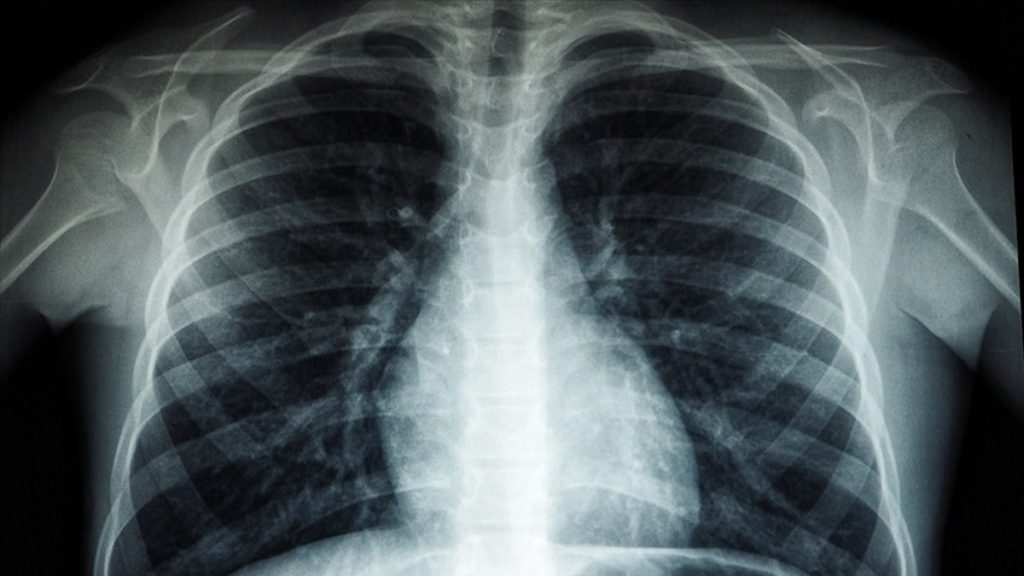

Bu sendromu, akciğerlerin ani bir şekilde iltihaplanması sonucu oluşan, hayati organlara yeterli oksijen gitmeyen ciddi bir durumdur.

Akciğerde kalsiyum birikirse (kalsiyum oksit, kalsiyum karbonat, kalsiyum sülfat gibi kimyasallara uzun süreli maruz kalınan mesleklerde) akciğer filminde beyaz lekelenmeler görülür.